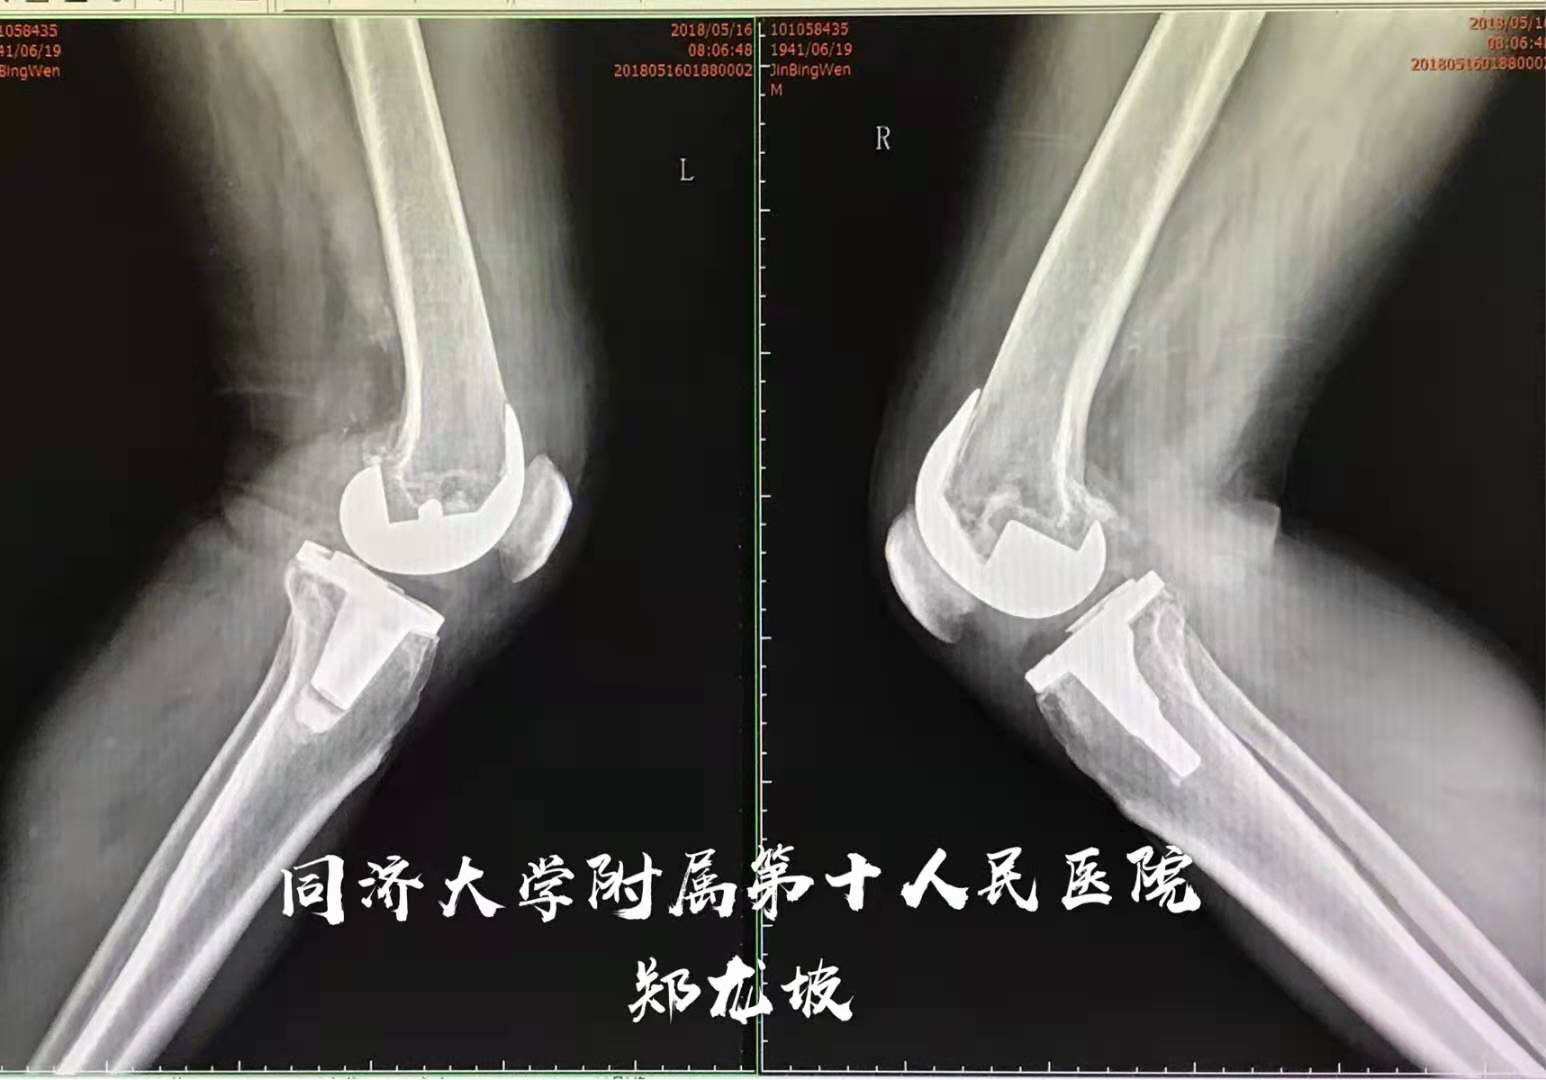

于2018年5月再行左侧膝关节表面置换

术后双下肢力线得到矫正